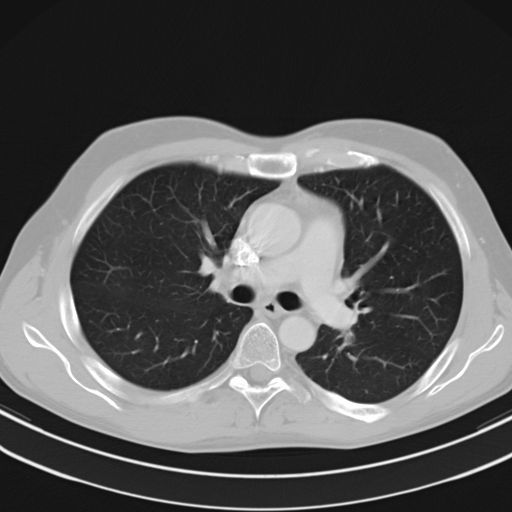

CT-scan van de thorax

Hier wordt een beeld gevormd van de structuren van de borstkas. De longen, het mediastinum maar ook de bloedvaten en het hart worden beoordeeld. Tijdens het onderzoek zal de patiëtn gevraagd worden om de adem in te houden. Dit om een egaal opvolging van de beelen te krijgen. Ook is het uiteraard van belang om tijdens het onderzoek niet te bewegen. Door de steeds toenemende snelheid van de toestellen is dit echter niet een zware opdracht. Als je denkt dat een volledig longscan ongeveer een kleine dertig seconen in beslag neemt. Het kan echter zijn dat er volledigheidshalve een tweede opname wordt genomen, blijven liggen tot men u zegt dat het afgelopen is, is dus wel da boodschap.

Afhankelijk van de indicatie wordt er al dan niet besloten om contrast toe te dienen.

Ook hier is het dan nodig om de patiënt nuchter te houden ten minste vier uur voor het onderzoek.